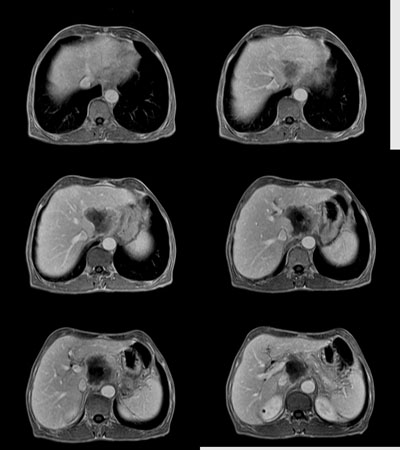

男:62岁:右上腹痛1月。b超报告肝左叶外侧段占位。请讨论灶来源!谢谢!!

肿块对周围结构是推移改变,囊变,强化不明显,不考虑来源于胰腺,后腹膜占位,期待结果

肿块对周围结构是推移改变,囊变,强化不明显,不考虑来源于胰腺,后腹膜占位,考虑为腹膜后纤维瘤。

腹主动脉前肝左叶后方占位,局部与肝脂肪间隙尚存,故排除左肝来源病变.病灶主体层面位置较高,胰腺受压前移.腹腔干明显拉长包埋.增强后肿瘤边缘性强化.胃小弯侧血管明显增粗.

考虑;后腹膜来源肿瘤.神经源性肿瘤>间叶源性肿瘤>淋巴源性肿瘤.